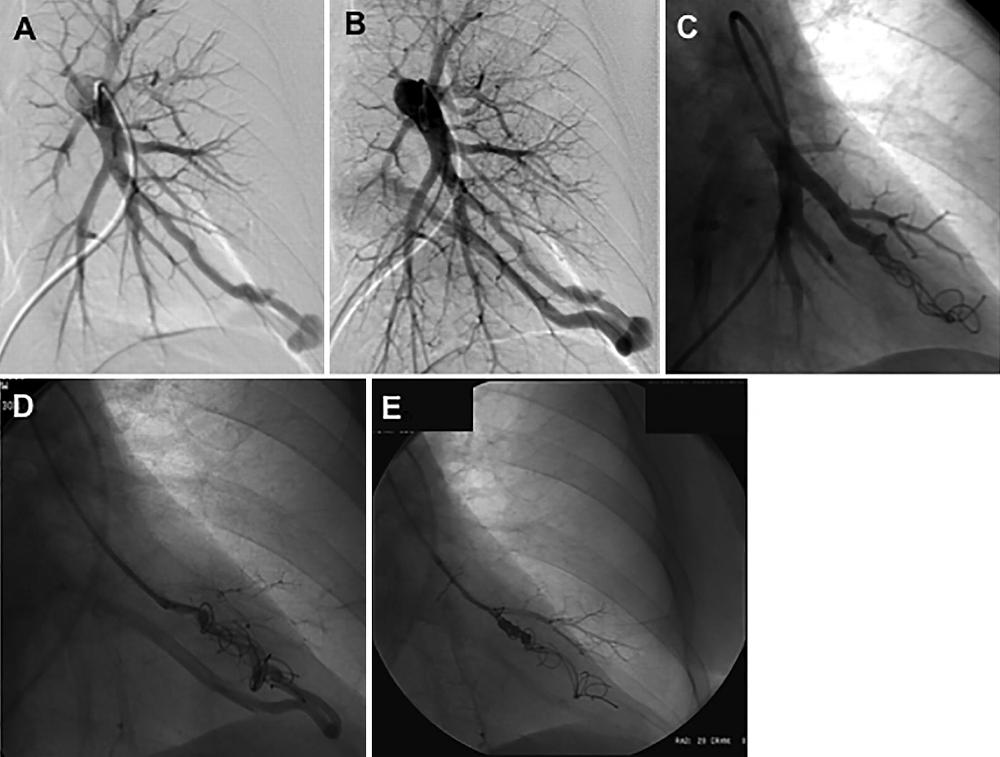

Figure 2. Images in a 52-year-old woman with hereditary hemorrhagic telangiectasia demonstrating on left pulmonary artery angiogram an arteriovenous malformation (AVM) at, A, B, the left base. C, Selective angiogram after embolization of the AVM by using coils. D, E, Angiogram shows embolization for persistence treated with repeat embolization performed 2 years after initial embolization.